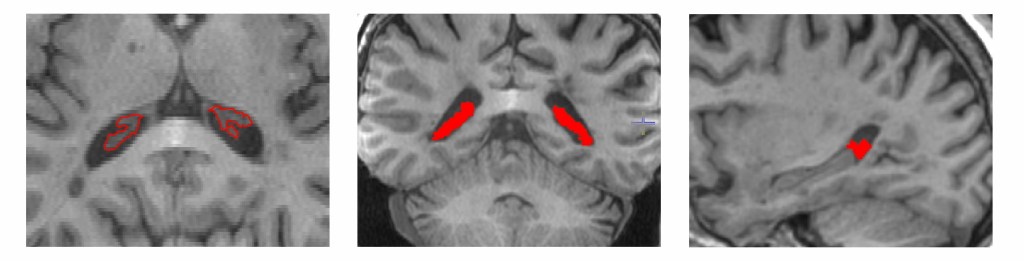

This longitudinal study reveals how ongoing tissue damage within chronic MS lesions contributes to brain atrophy, offering new insights into disease progression even in treated patients.

- Used advanced diffusion tensor imaging to track microstructural changes over time

- Developed methods to precisely analyze lesion cores separate from edges

- Created techniques to account for brain atrophy when measuring lesion changes

- Established ways to quantify progressive tissue damage in stable lesions